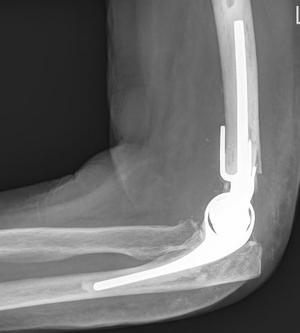

Elleboog artrose: totale elleboog prothese

Elleboogprothese